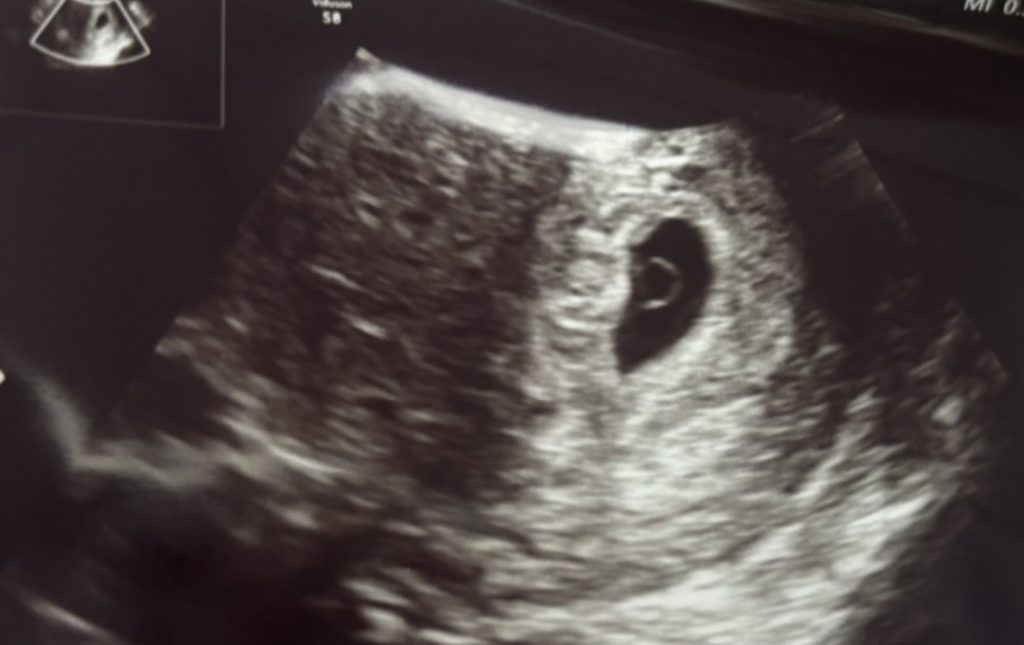

この日のエコー写真はこちらです。

エコー写真(8週5日)

前回と比にならないくらい大きくなっていて驚きました。

頭が下で下半身が上です。

CRLが前回の胎嚢の大きさくらいになってます。